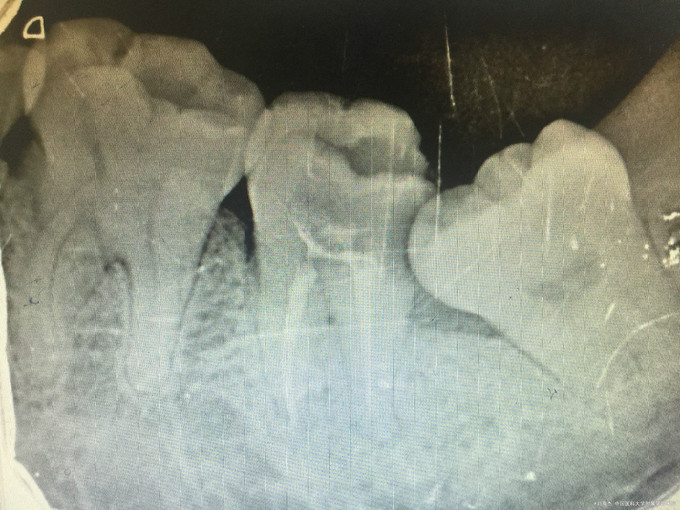

临床检查:37远中邻面龋坏,探疼(+),冷(++),叩(-),松动度(-),牙周正常. 38阻生齿未完全萌出。 辅助检查:X线示37龋坏累积髓腔,38近中阻生。

诊断:37牙髓炎,38阻生齿。 治疗:经患者知情同意后,37局麻去腐降牙合,开髓拔髓寻找根管口,建立直线通路,扩通根管,确定工作长度。vdw/EDTA凝胶镍钛器械,低浓度次氯酸钠冲洗根管,预备至25/06,氢氧化钙诊间封药,一周后复诊,试主尖X线示恰充,试干根管,导AH-PLUS糊剂,VDW热压胶垂直加压根充,术后见根管恰充,暂封调合抛光。择期拔除38.